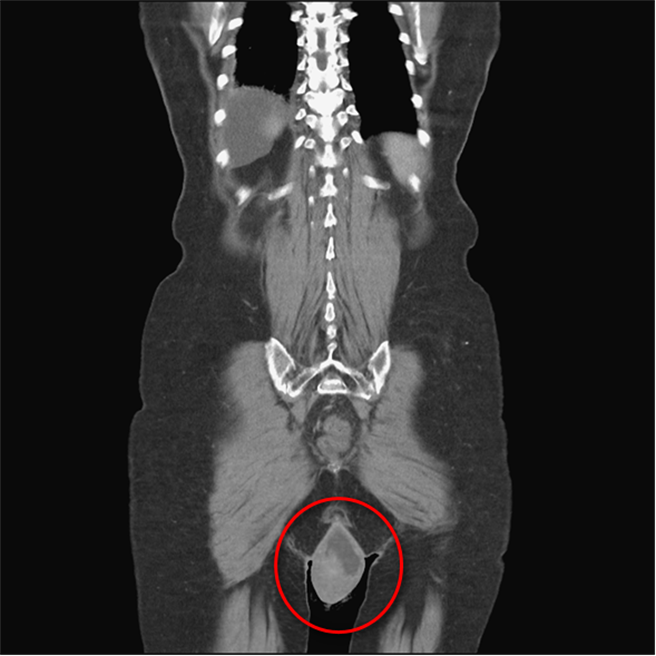

台中一名70岁刘姓妇人患有失智症,且有肝硬化导致腹腔压力过大,导致骨盆腔中的阴道脱垂,露出体外近20CM,也因下体不适走路「卡卡」,经检查后发现妇人因脱垂子宫也有发炎与糜烂的症状,台中医院妇产科医师林新旺利用「棘韧带悬吊术」手术,改善骨盆腔与阴道脱垂问题,让妇人行动自如。

台中医院妇产科医师林新旺表示,骨盆腔肌肉松驰会导致骨盆腔脱垂,让骨盆腔里如子宫、膀胱、阴道等器官,滑脱出体外,加上刘妇本身有腹水、肺积水的症状,虽然还能走,但因为脱垂的关系,行动比较不灵敏,且内科疾病带来的腹部积水症状,会让腹腔压力增加,因此症状特别严重,下体脱垂近20公分,并出现子宫发炎等现象。

林新旺解释,失智长者因记忆与行动退化,难以用运动的方式来减缓骨盆腔脱垂,或使用子宫托来改善症状,且因刘妇腹腔压力过高,施作一般剖腹手术处理症状会使腹水溢出,因此只能从阴道进入施作棘韧带悬吊术手术,将骨盆腔器官吊起来解决脱垂的问题。

林新旺说,目前若想以手术改善脱垂,棘韧带悬吊术是比较主流且有效的方式,由于骨盆腔的肌肉松弛是全面的,即使患者割除子宫,膀胱或直肠等器官还是有可能下坠,因此要治疗脱垂,并非拿掉子宫就好,还是要想办法将骨盆腔器官「扶」到较理想的位置,才能改善问题。